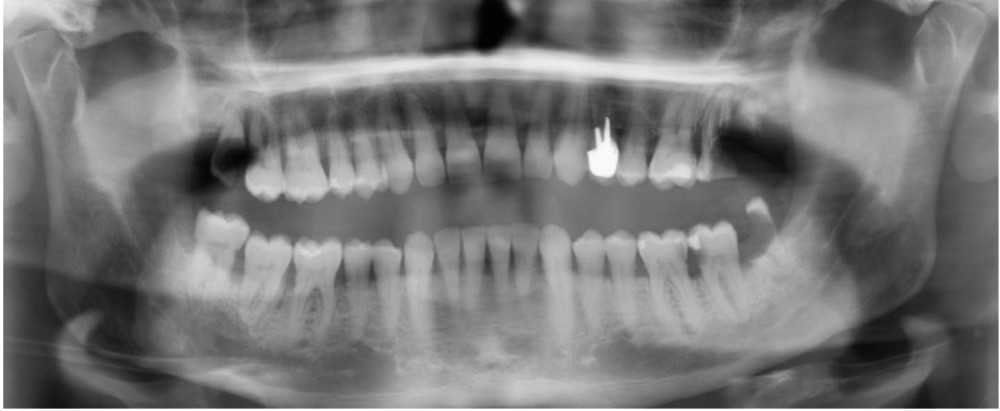

Dans le bilan avant mise en place du traitement, les recommandations, notamment de rhumatologie, indi-quent la réalisation d’un bilan dentaire et la mise en œuvre des soins nécessaires [1]. Cela a pour but d’identifier les foyers infectieux en présence et de les prendre en charge avant que le traitement ne débute, donc avant que le patient présente un risque infectieux accru (fig. 2).

L’attitude face à ces foyers infectieux, au-delà du pronostic de chaque dent, dépendra de facteurs, généraux notamment : thérapeutique mise en place (donc risque infectieux précis pour le patient), durée estimée du traitement (et donc du risque), le pronostic de la pathologie, la présence de facteurs de risque majorant le risque infectieux ou encore la compliance du patient [2].